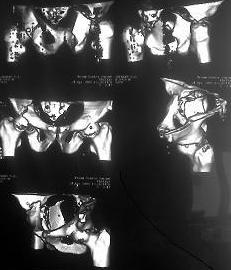

Добрый день ув.коллеги. Теперь подробнее.В нашем отделении находится пациент с тяжелой сочетанной травмой (множественные переломы ребер, тупая травма живота с повреждением печени, селезенки) с нашей стороны тяжелая травма таза.С момента травмы прошло 3 недели.при поступлении в экстренном порядке пациентом занимались хирурги, затем проводилось интенсивное лечение в реанимации. сначала боролись с двухсторонним гемопневмотораксом, потом с пневмонией. В течении всего времени пациент находился в положении по Волковичу, других мер не принималось (почему не знаю). На сегодняшний день состояние больного стабильное, удовлетворительное.пневмония разрешилась, проблем по животу и легким нет, по анализам компенсирован. На представленной R-мме и КТ если я правильно расценил: справа имеется полный внутрисуставной двухколонный перелом, низкий вариант(С2)., слева поперечный перелом вертлужной впадины(В10) без смещения.(извините за качество, снято с телефона)Хотелось бы услышать ваше мнение, предложения по поводу лечения перелома костей таза. Стоит ли оперировать левую вертлугу? Чем предпочтительнее зафиксировать перелом справа? Заранее спасибо. С ув.Андрей.

сделать стандартные проекции Judet и отфотографировать их в лучшем качестве, увеличить микропленку, выложить срезы на уровне свода вертлужных впадин.